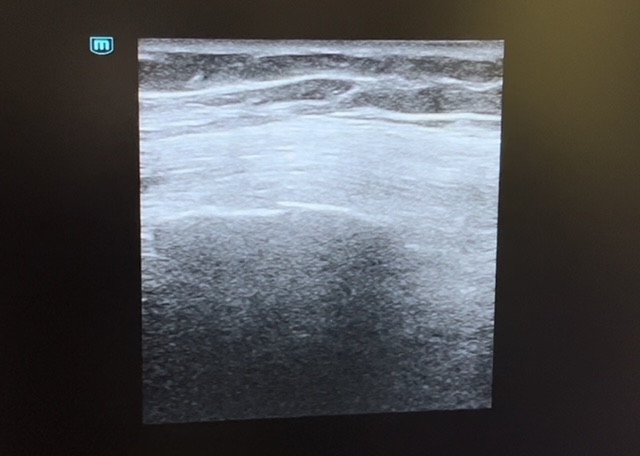

Descripción de los hallazgos ecográficos y las imágenes más relevantes para la resolución del caso

Se evidencia en la ecografía pulmonar sobre el 7º y 8º arco costal izquierdo una posible línea de fractura con falta de contigüidad en los rebordes costales sin evidenciar signos de neumotórax.